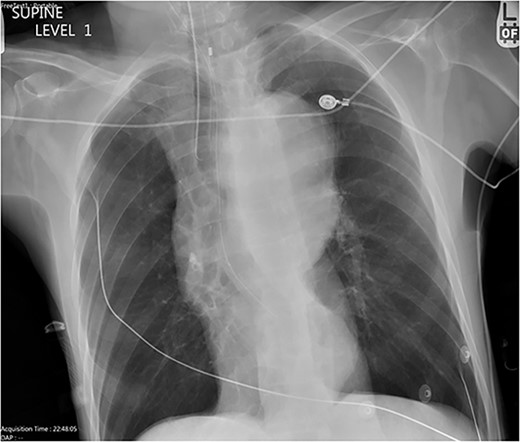

A 59-year-old male with no known previous medical history presented to a Level 1 trauma center after being discovered by EMS in a large volume of red blood. The event was unwitnessed by bystanders, so it was assumed that the mechanism was a traumatic fall with a resulting head bleed. During transportation patient lost pulses but returned to spontaneous circulation after cardiopulmonary resuscitation. The patient’s initial vital signs in the trauma bay were a blood pressure of 129/40 mmHg, a heart rate of 101 beats/min, and a Glasgow Coma Score of 3. The head was bandaged by EMS with red blood sticking to the patient’s hair, ears, and face. Upon unwrapping of the patient’s bandaged head, there was no source of bleeding nor was any trauma identified to the body. The patient was intubated and an orogastric tube was inserted with immediate drainage of 2L of bright red blood. The initial differential diagnosis was trauma in origin, including a basilar skull fracture with ingestion of blood or blunt abdominal trauma. Sonography identified no signs of internal peritoneal bleeding. Chest X-ray revealed large dilation of the thoracic aorta (Fig. 1). CT of the chest with IV contrast showed aneurysmal dilation of the ascending and descending thoracic aorta with max diameter of 65 mm, AEF at the level of pulmonary artery bifurcation and contrast extravasation into the esophagus and stomach (Figs 2–4). Octreotide was given and a massive transfusion protocol (MTP) was initiated with transfusion including 2 units of whole blood and 15 units of RBCs. Cardiothoracic surgery and interventional radiology were called to evaluate the patient; however, massive blood loss ultimately led to a myocardial infarction and the patient expired 75 min after admission.

Chest X-ray with patient supine showing an impressive dilated thoracic aorta consistent with a large thoracic aneurysm.